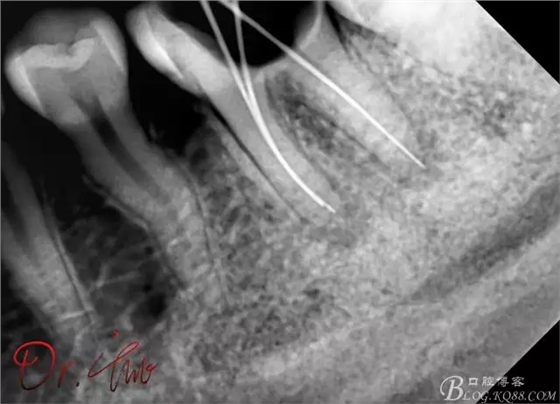

拍片確定長度

第一次試主尖